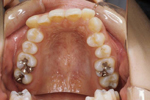

矯正の症例

| 【Before】 | 【After】 | |